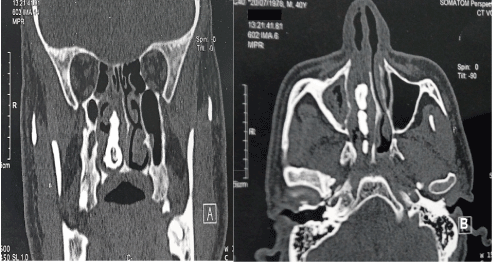

In order to better visualize the posterior extent of the mass and its contact with the mucosa, a maxillofacial CT scan was ordered, revealing a foreign body of calcium density in the right nasal cavity measuring 47/27/13 mm with an adjacent mucosal thickening. Associated with a right maxillary sinusitis and a right deviation of the nasal septum (Figure 2). Endoscopic removal of the rhinolith was performed under general anesthesia. histological evaluation of all the stone revealed acellular calcifications (calcium) consistent with rhinolithiasis.

Figure 2. Naso-sinus CT, on coronal (A) and on axial views, bone windows: foreign body of calcium density, located in the nasal fossa, interposed between the inferior turbinate and the nasal septum